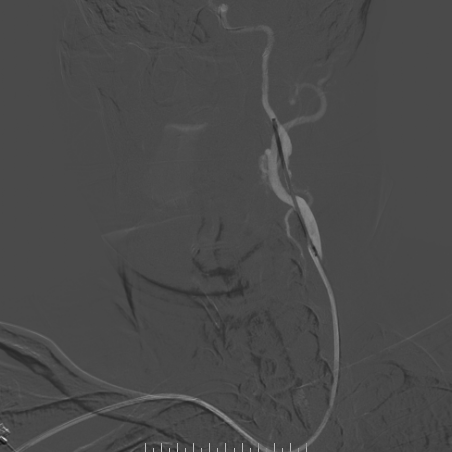

手术过程

-- 右侧桡动脉穿刺置入7F 泰尔茂薄壁鞘,波科7F0.081导引导管同轴5F 125cm SimmonsII导管在0.035导丝引导下引至左侧颈总动脉。

波科支架怎么样​径技·第165期|7F经桡入路下的颈动脉狭窄支架成形术一例_https://www.jmylbn.com_新闻资讯_第24张

波科支架怎么样​径技·第165期|7F经桡入路下的颈动脉狭窄支架成形术一例_https://www.jmylbn.com_新闻资讯_第25张

波科支架怎么样​径技·第165期|7F经桡入路下的颈动脉狭窄支架成形术一例_https://www.jmylbn.com_新闻资讯_第26张

-- 路途引导下,FilterWire EZ保护伞顺利通过狭窄段至左侧颈内动脉岩骨水平段,顺利释放保护伞

波科支架怎么样​径技·第165期|7F经桡入路下的颈动脉狭窄支架成形术一例_https://www.jmylbn.com_新闻资讯_第27张

波科支架怎么样​径技·第165期|7F经桡入路下的颈动脉狭窄支架成形术一例_https://www.jmylbn.com_新闻资讯_第28张

波科支架怎么样​径技·第165期|7F经桡入路下的颈动脉狭窄支架成形术一例_https://www.jmylbn.com_新闻资讯_第29张

--沿保护伞导丝引入波科4mm*30mm-Sterling球囊跨狭窄段扩张后,交换9mm*40mm-Wallstent支架经波科7F导引导管顺利到达狭窄段,跨狭窄段缓慢平稳释放。

波科支架怎么样​径技·第165期|7F经桡入路下的颈动脉狭窄支架成形术一例_https://www.jmylbn.com_新闻资讯_第30张

波科支架怎么样​径技·第165期|7F经桡入路下的颈动脉狭窄支架成形术一例_https://www.jmylbn.com_新闻资讯_第31张

波科支架怎么样​径技·第165期|7F经桡入路下的颈动脉狭窄支架成形术一例_https://www.jmylbn.com_新闻资讯_第32张

-- 支架释放后残余狭窄稍高,再次交换引入波科4mm*30mm-Sterling球囊行支架内后扩张,使用5F 125cm多功能回收保护伞,复查造影示狭窄明显改善,前向血流通畅。

波科支架怎么样​径技·第165期|7F经桡入路下的颈动脉狭窄支架成形术一例_https://www.jmylbn.com_新闻资讯_第33张

波科支架怎么样​径技·第165期|7F经桡入路下的颈动脉狭窄支架成形术一例_https://www.jmylbn.com_新闻资讯_第34张

波科支架怎么样​径技·第165期|7F经桡入路下的颈动脉狭窄支架成形术一例_https://www.jmylbn.com_新闻资讯_第35张

-- 术后即刻正侧位造影示左侧颈内起始部狭窄明显改善,支架内血流通畅,远端分支显影正常。